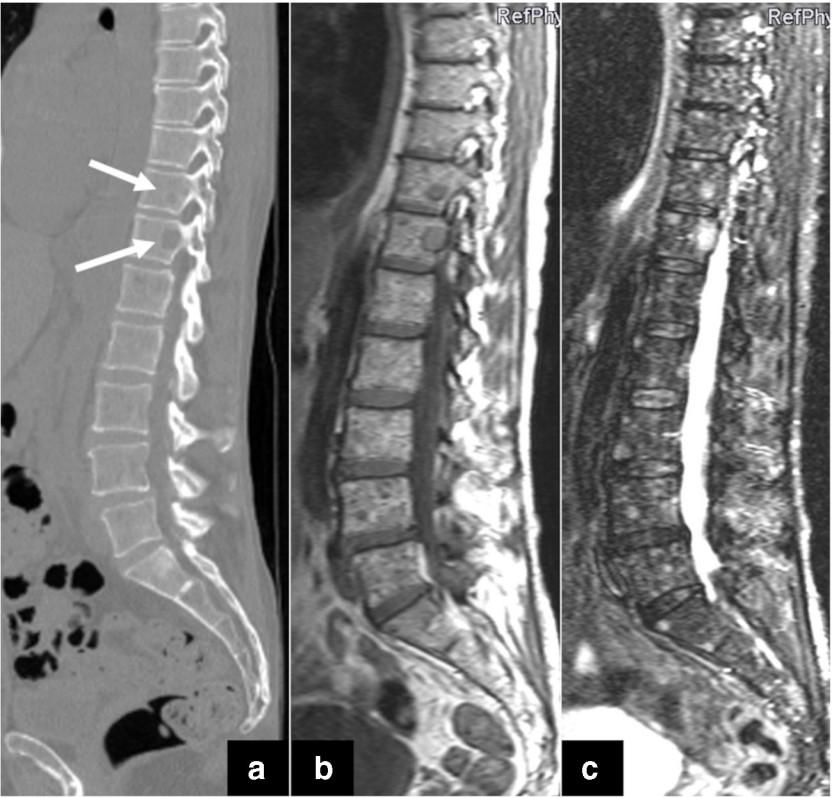

Skeletal CT scan

K. Treiti et al. Skeletal Radiology 2021

MRI Scan

PET/CT Imaging in MM

Stewart AK et al. Blood. 2009;114:5436. San Miguel JF et al. ASCO Educational Book. 2013;e313.